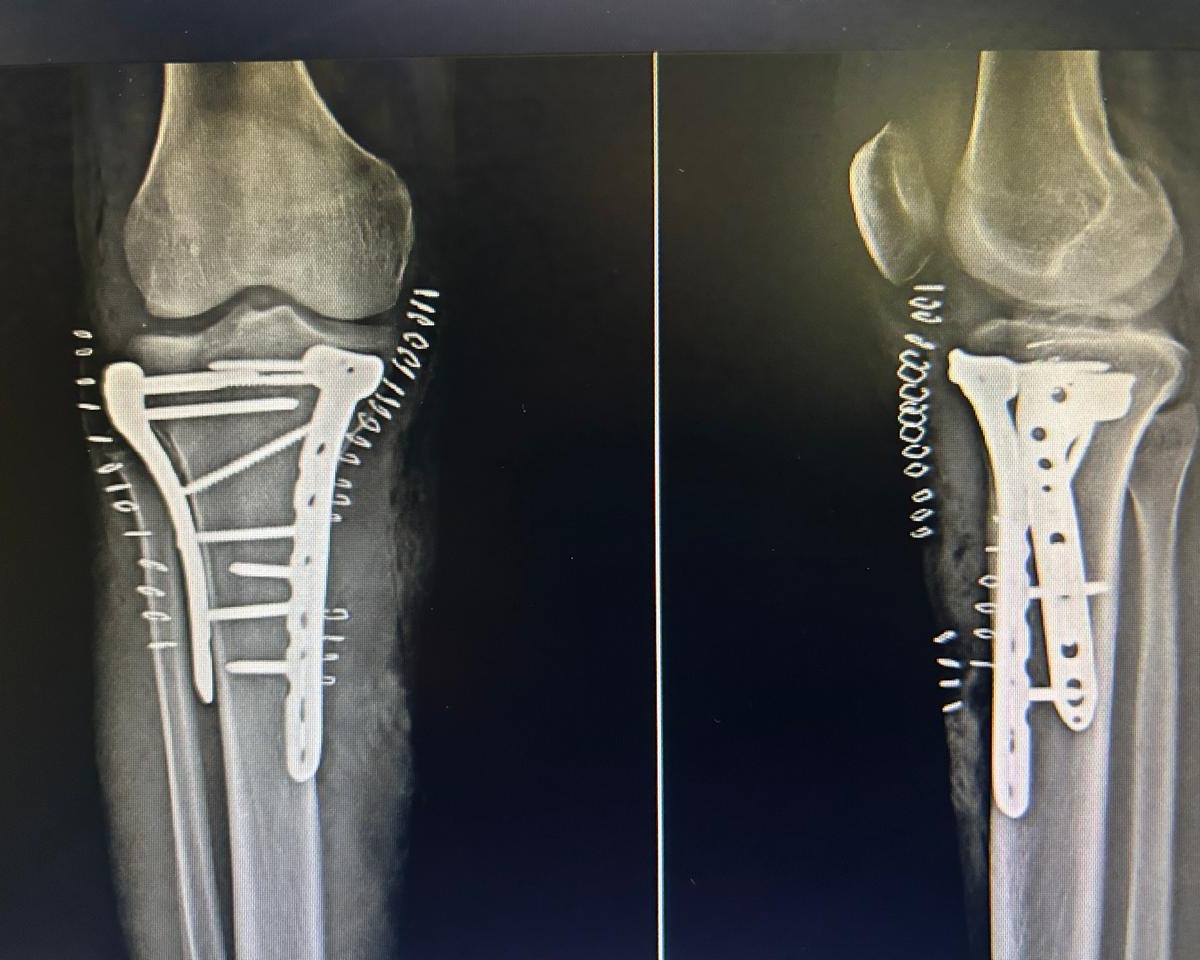

IMPLANT REMOVAL